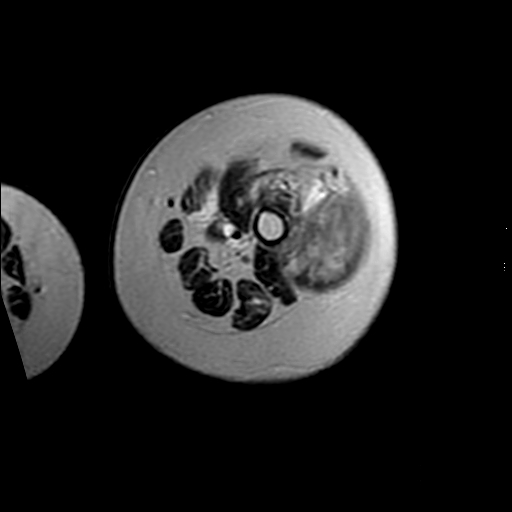

左侧大腿外伤10余年,当时情况不清,发现左侧大腿肿胀7年余,而后又有多次外伤史,近1年来出现疼痛,减重半年。查体:左侧大腿肿胀明显,皮温、肤色正常。

增强

软组织肿块,股骨破坏,增强不均匀强化-----支持恶性肿瘤